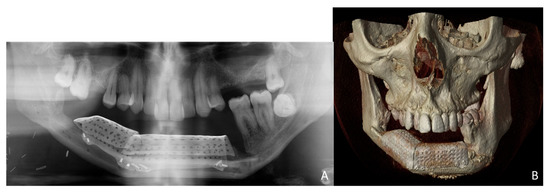

Simultaneously, a cortico-cancellous graft of the left anterosuperior iliac crest was obtained. The graft was fixed to the fibula using the CAD/CAM titanium mesh and 1.5 mm screws (Figure 5B). There was no intraoral exposure of the graft and an increase in the vertical dimension of the fibula was achieved and demonstrated by panoramic radiograph and CT scan (Figure 6A,B and Figure 7A,B).

The prosthetic rehabilitation was carried out by means of a fixed implant-supported prosthesis providing normal occlusion (Figure 10B and Figure 11A). Three years later, there was no evidence of significant peri-implant bone resorption (Figure 11B). The prosthetic rehabilitation allowed a correct aesthetic and functional result with a regular diet and intelligible speech (Figure 12A,B).

CT Scan and CBCT were performed in the postoperative follow-up, and bone volume and bone resorption (Figure 13 and Figure 14) were evaluated by the Radiology Department of the hospital. A morphing reconstruction was performed to compare the lower facial third showing an improvement in the aesthetic profile and facial projection (Figure 15).

Figure 6. Postoperative images after 3D reconstruction with CAD/CAM titanium mesh and iliac crest graft. (A) Panoramic radiograph showing the vertical reconstruction of the symphysis and both mandibular bodies with the iliac crest graft. (B) CT Scan with three-dimensional reconstruction of the mandible.

Figure 11. Functional result. (A) Final dental restoration. (B) Panoramic radiograph demonstrating the reconstruction of the previous height of the mandible with a correct osseointegration of the implants.